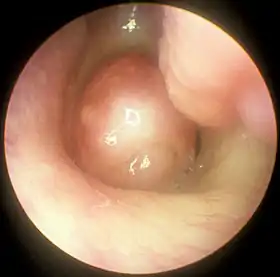

![]() Large nasal polyp (round mass, center), which is commonly treated and removed by FESS | |

Functional endoscopic sinus surgery is most commonly used to treat chronic rhinosinusitis (CRS),[7] only after all non-surgical treatment options such as antibiotics, topical nasal corticosteroids, and nasal lavage with saline solutions[8] have been exhausted. CRS is an inflammatory condition in which the nose and at least one sinus become swollen and interfere with mucus drainage.[8] It can be caused by anatomical factors such as a deviated septum or nasal polyps (growths), as well as infection. Symptoms include difficulty breathing through the nose, swelling and pain around the nose and eyes, postnasal drainage down the throat, and difficulty sleeping.[9] CRS is a common condition in children and young adults.[10]

The purpose of FESS in treatment of CRS is to remove any anatomical obstructions that prevent proper mucosal drainage. A standard FESS includes removal of the uncinate process, and opening of the ethmoid air cells and Haller cells[11] as well as the maxillary ostium, if necessary. If any nasal polyps obstructing ventilation or drainage are present, they are also removed.[7] In the case of paranasal sinus/nasal cavity tumors (benign or cancerous), an otolaryngologist can perform FESS to remove the growths, sometimes with the help of a neurosurgeon, depending on the extent of the tumor. In some cases, a graft of bone or skin is placed by FESS to repair damages by the tumor.[12]